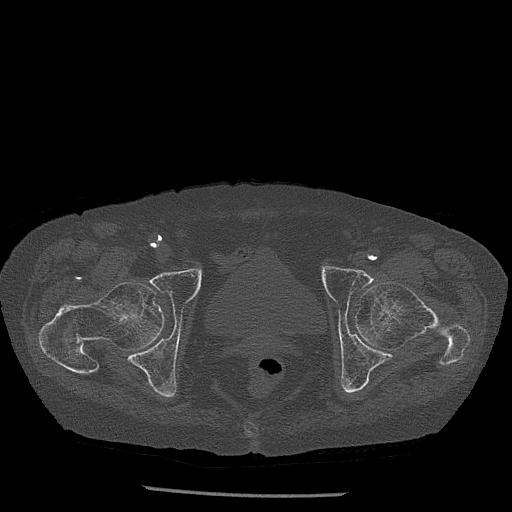

100703 1/27 両股正面+軸 1/29 両股正面+軸 94歳女性 パンソンロン